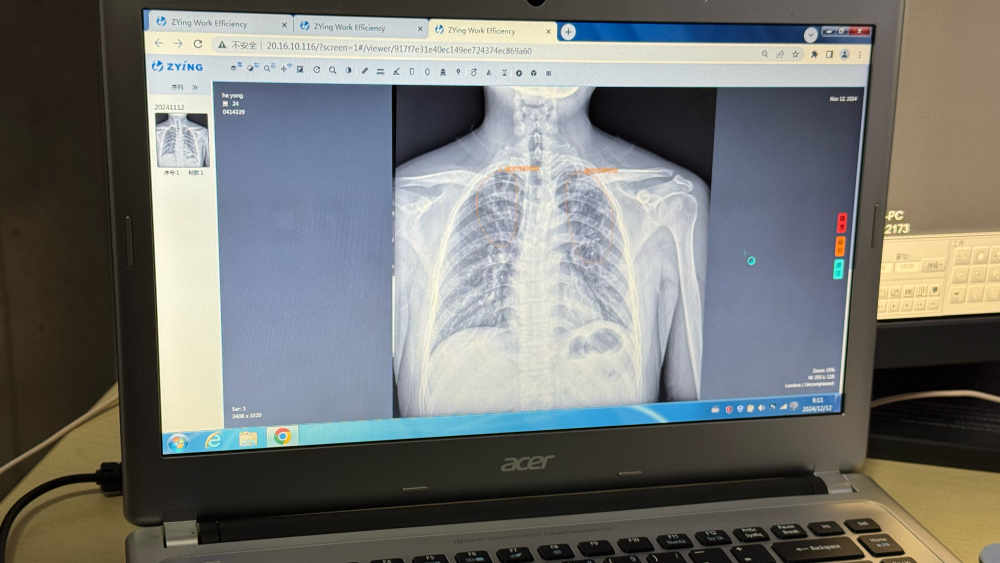

記者在江蘇省走訪時看到,通過將人工智能閲片模型裝入影像科雲平台,全省所有公立醫院和部分民營醫院的醫療機構實現互聯互通,能夠快速篩查患者胸片可疑病灶,並生成自動化報告。

“AI賦能有效提高篩查效率和診斷精確度,尤其是在基層醫療機構發揮了重要作用。”江蘇省疾控中心慢性傳染病預防控制所所長竺麗梅説。

江蘇省崑山市第一人民醫院錦溪分院放射科AI雲平台閲片系統。新華社記者顧天成 攝

從AI篩查到全程數據管理,再到全自動一體化微型核酸檢測系統,科技不僅優化了傳統篩查流程,也為“無結核社區”建設、實現“首診即確診”提供了創新解決方案。

江蘇省崑山市第一人民醫院錦溪分院放射科主任湯青燕表示,AI技術不僅能為肺結核篩查提供支持,還促進了包括肺炎、肺癌在內的多種肺部疾病早期發現和診斷。